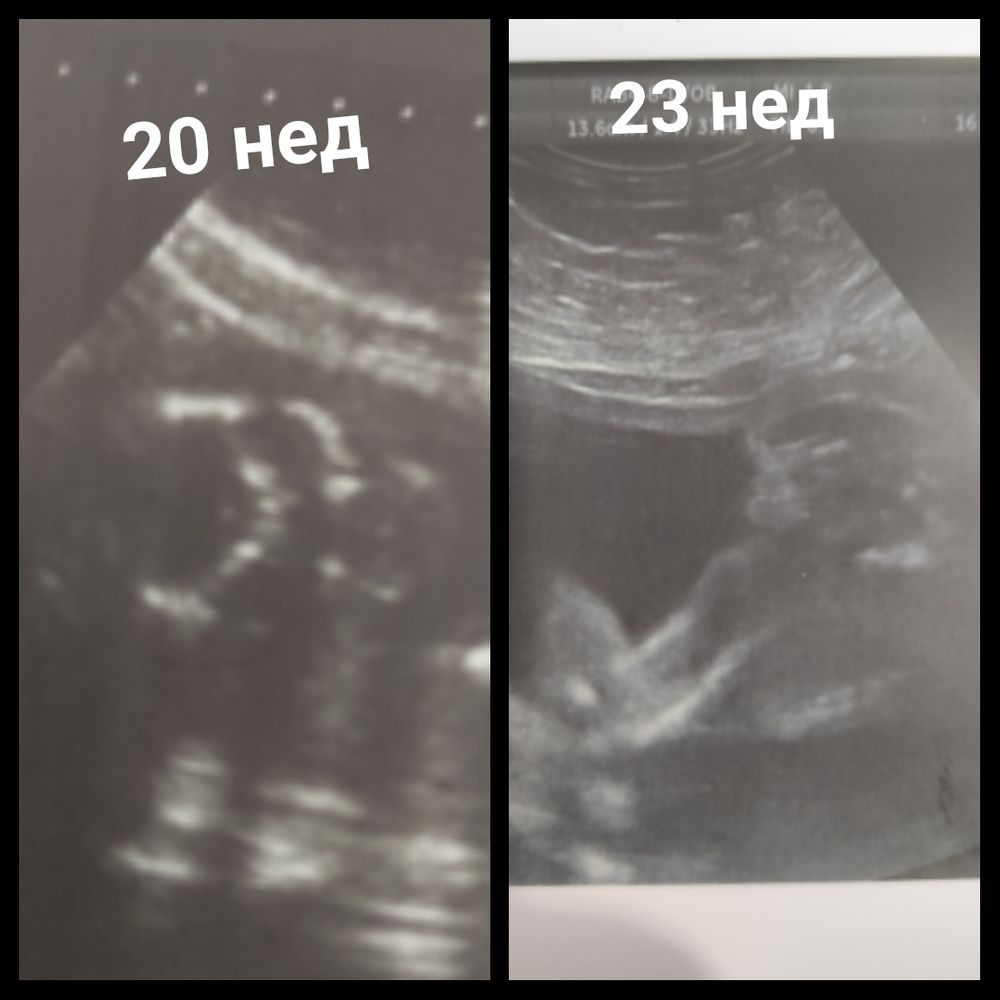

Dilyara, моя 17 недель и сестренкина 16.3. По-моему, тут очевидно 😁😁 Изображение Изображение

16.07.2022

Марина, ну все, я теперь еще больше уверенна, что девочка.. Оказывается с девочками УЗИ так похожи у всех.